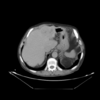

| (b) Portal venous phase (template dataset, ) | (c) Registered template, (CR-based method) | (d) Registered template, (proposed method) | |

| Figure a: Arterial phase (reference dataset, ) | |||

For the assessment of the proposed method, we carry out a comparison with the purely intensity-based variational method recently presented by the authors of this work in [26]. This CR-based approach was reported to outperform publicly available state-of-the art methods such as Elastix and ANTs in the medical setting. As can be seen in Fig.1, the proposed framework shows excellent results for the three considered registration scenarios (arterial-portal, arterial-non-contrast and portal-non-contrast), reaching average values of 1.47, 1.44 and 1.52 bits in terms of mutual information, corresponding to the arterial-portal, arterial-non-contrast and portal-non-contrast cases, respectively; this represents a mean improvement of 28.9%, 48.45% and 51.16% in relative terms of mutual information, thus outperforming the CR-based registration algorithm, which achieves a mean improvement of 26.48%, 44.22% and 43.25%, respectively. Additionally, due to the analogous behavior (i.e., comparable final values of mutual information) of the proposed method in the three scenarios, all available experiments can be grouped into one ensemble in order to assess a more comprehensive validation of the actual registration error. A ground truth was established by an expert in the form of identifiable anatomical locations (landmarks) for all experiments. The registration errors were then obtained by computing the spatial distance between the corresponding landmarks in the reference and registered template datasets. Figures Fig.2(a) and Fig.2(b) show through box plots the registration error (in millimeters) achieved by the methods under comparison, gathering the results from the three considered registration scenarios. These box plots collect the final spatial distances between corresponding landmarks, along with the median distance error and its statistical significance (notch showing the 95% confidence interval of the true median). According to Fig.2(b), the proposed method significantly improves on the registration error of the CR-based approach, since it reduces the initial median error from 9.50 mm to a residual median distance between landmarks of 1.41 mm, decreasing at the same time the outliers occurrence.

In addition to the previous measurements, the visual outcomes of two of the experiments are shown in figures Fig.3 and Fig.4, whose purpose is to highlight the most illustrative differences (from a medical point of view) between the results provided by the compared methods. In Fig.3, we observe a normal size of the liver, with discretely irregular contours and homogeneous signal intensity. In hepatic segment II, there is a lesion of 40 mm of maximum axis, encapsulated and with well-defined contours and heterogeneous enhancement in arterial phase (after administration of intravenous contrast), suggestive of hepatocellular carcinoma (HCC). In this slice of the CT scan, we can also observe the aorta that shines in the arterial phase, the lower area of the stomach and the upper area of the spleen. In Fig.4, the liver has a normal size with discretely irregular contours in relation to changes due to chronic liver disease. In hepatic segment IV, a 36 mm diameter focal lesion is identified, which has arterial phase enhancement with a small area of necrosis of 13 mm; it corresponds to a HCC previously chemoembolized with partial necrosis. In this slice of CT, we can also observe the aorta, the gastric chamber and the spleen. When comparing the two methods under study, it can be seen how in Fig.3 the resulting registered datasets are very similar. However, looking closely, it can be noticed that in the right part of the image (left side of the patient) the shape and width of the structures corresponding to the stomach and the spleen in Fig.3(d) match better those in the reference dataset. Likewise, the part of the rib at the upper right of the image is more similar to the same region in the reference dataset by using the proposed method. Regarding the experiment shown in Fig.4, it can be easily appreciated how the geometrical matching (with respect to the reference dataset, Fig.4(a)) of the structures in the right side of the image (specially the gastric chamber) is visually more satisfactory in Fig.4(d). Moreover, the area of tumor necrosis which results from the proposed method is also slightly better aligned.